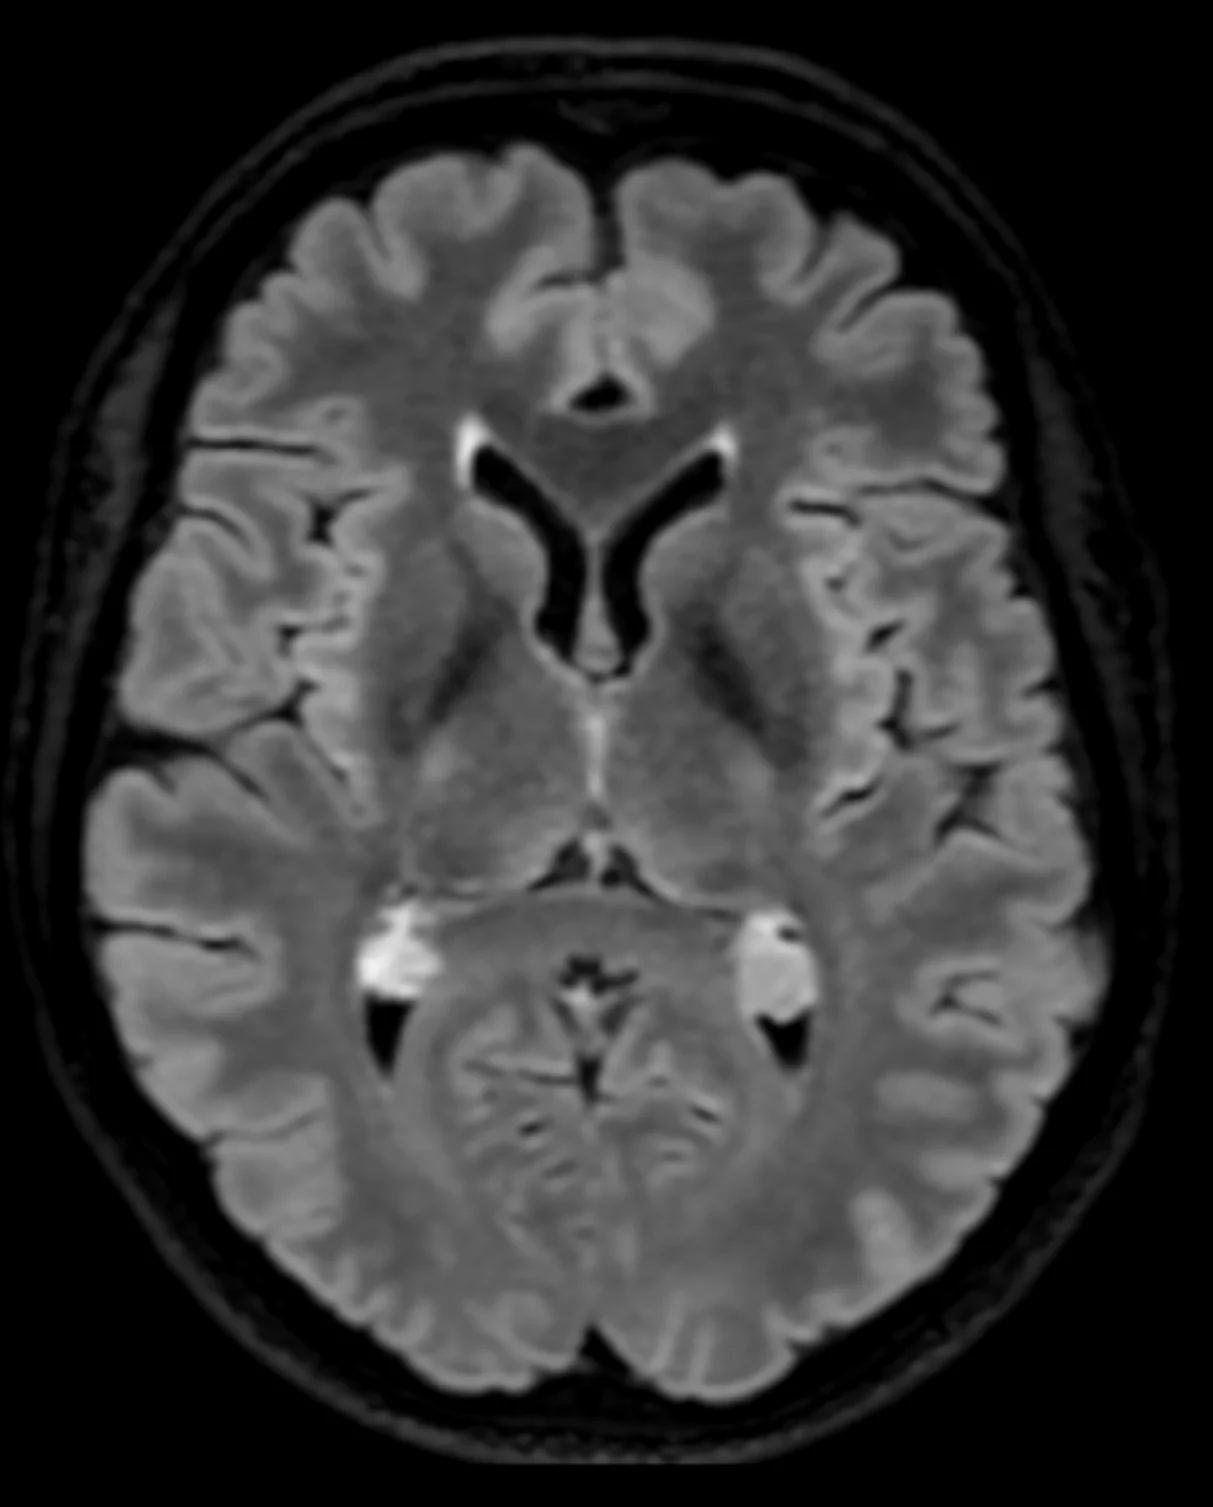

- Kernspintomographie (MRI, MRT)

- Abklärung und Beratung bei Gefässfehlbildungen (Aneurysma, arteriovenöse Malformation, arteriovenöse Fistel)